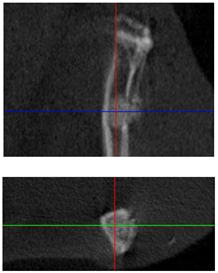

| Figurative Point | |||

|---|---|---|---|

| 3 | 5 | 8 | |

| 3D model and orthogonal projections Initial | ![]() | ![]() | ![]() |

![]() | ![]() | ![]() | |

| 3D model and orthogonal projectionsAfter implantation period of 3 months | ![]() | ![]() | ![]() |